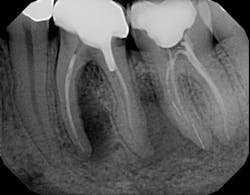

2. What is the clinical/radiographic presentation?

d. Is the bone loss vertical or horizontal, and what is the severity?